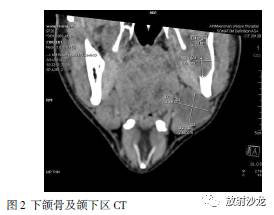

下颌骨及颌下区CT(见图2)示:左下颌骨及颌下区低密度占位,考虑囊肿可能。CT中可见左下颌骨近下颌角区局限性骨质破坏,提示肿块可能来源于下颌骨,体检时扪及的颌下区肿物可能是受压下移的左侧颌下腺。